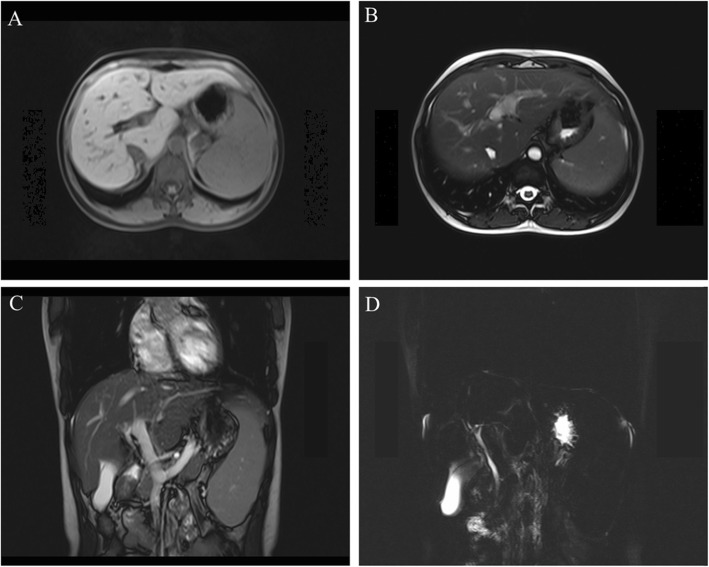

After admission to our department, we found that the patient had no jaundice, pruritus, asthenia, anorexia, and other discomforts. She denied a history of alcohol intake and use of any hepatotoxic drugs. She also had no family history of liver disease. On physical examination, mild splenomegaly was observed. The results of the rest of the examinations were unremarkable. Her laboratory data (October 18, 2018) showed the following values: alanine aminotransferase, 62 U/L; aspartate aminotransferase 45 U/L; alkaline phosphatase, 300 U/L; γ-GT, 119 U/L; total bilirubin, 14.9 μmol/L; direct bilirubin, 4.7 μmol/L; and albumin, 43.9 g/L. The hepatitis virus markers (hepatitis A, B, C, and E) were negative. Antibodies against the cytomegalovirus and Epstein-Barr virus were also negative. Her ceruloplasmin and serum copper levels were normal, and no Kayser-Fleischer ring was observed upon examination by an experienced ophthalmologist. The qualitative urinary porphyrin test result was negative. All autoimmune antibodies, including antimitochondrial, antinuclear, and antineutrophil cytoplasmic antibodies, were negative. The serum α-1-antitrypsin concentration, thyroid function, coagulation function, and other laboratory investigation results were normal. Abdominal magnetic resonance imaging revealed liver cirrhosis, portal hypertension, splenomegaly, and cholestasis. No obstructions of the intrahepatic and extrahepatic bile ducts were found after further examination with magnetic resonance cholangiopancreatography (Fig. 1). With the consent of the patient, we performed a liver pathological examination. Histological analysis revealed that the MDR3 protein staining decreased significantly as compared with that in healthy persons (Fig. 2).

Fig. 1.

Liver magnetic resonance image. The abdominal magnetic resonance image shows liver cirrhosis, portal hypertension, splenomegaly, and cholestasis. No obstruction of the intrahepatic and extrahepatic bile ducts was found after further magnetic resonance cholangiopancreatographic examination